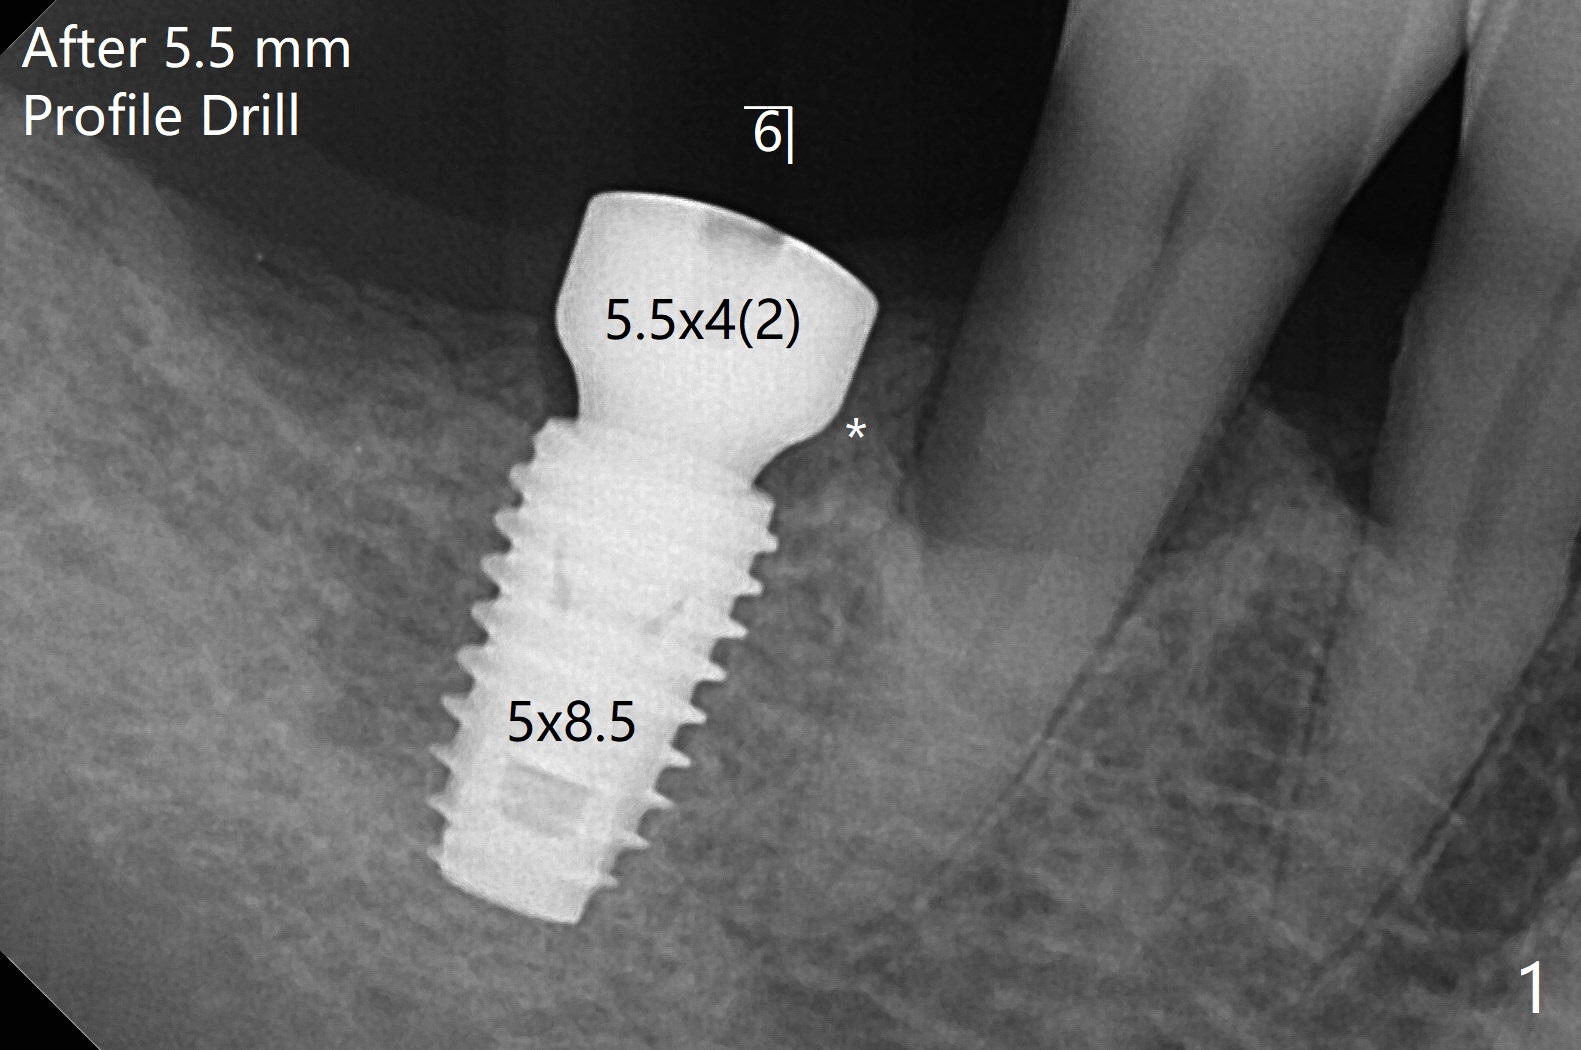

愈合基台与牙槽嵴

在导板指引下,5x8.5 毫米植体在右下6植入,临床检查证实牙槽嵴下,使用5.5毫米Profile Drill后,放置5.5x4(2)毫米愈合基台,后者好像与近中牙槽嵴没有明确分离(图一:*;可能脱落或者造成骨质吸收)。放入5x7毫米基台,分离明显(图二(牙周敷料))。